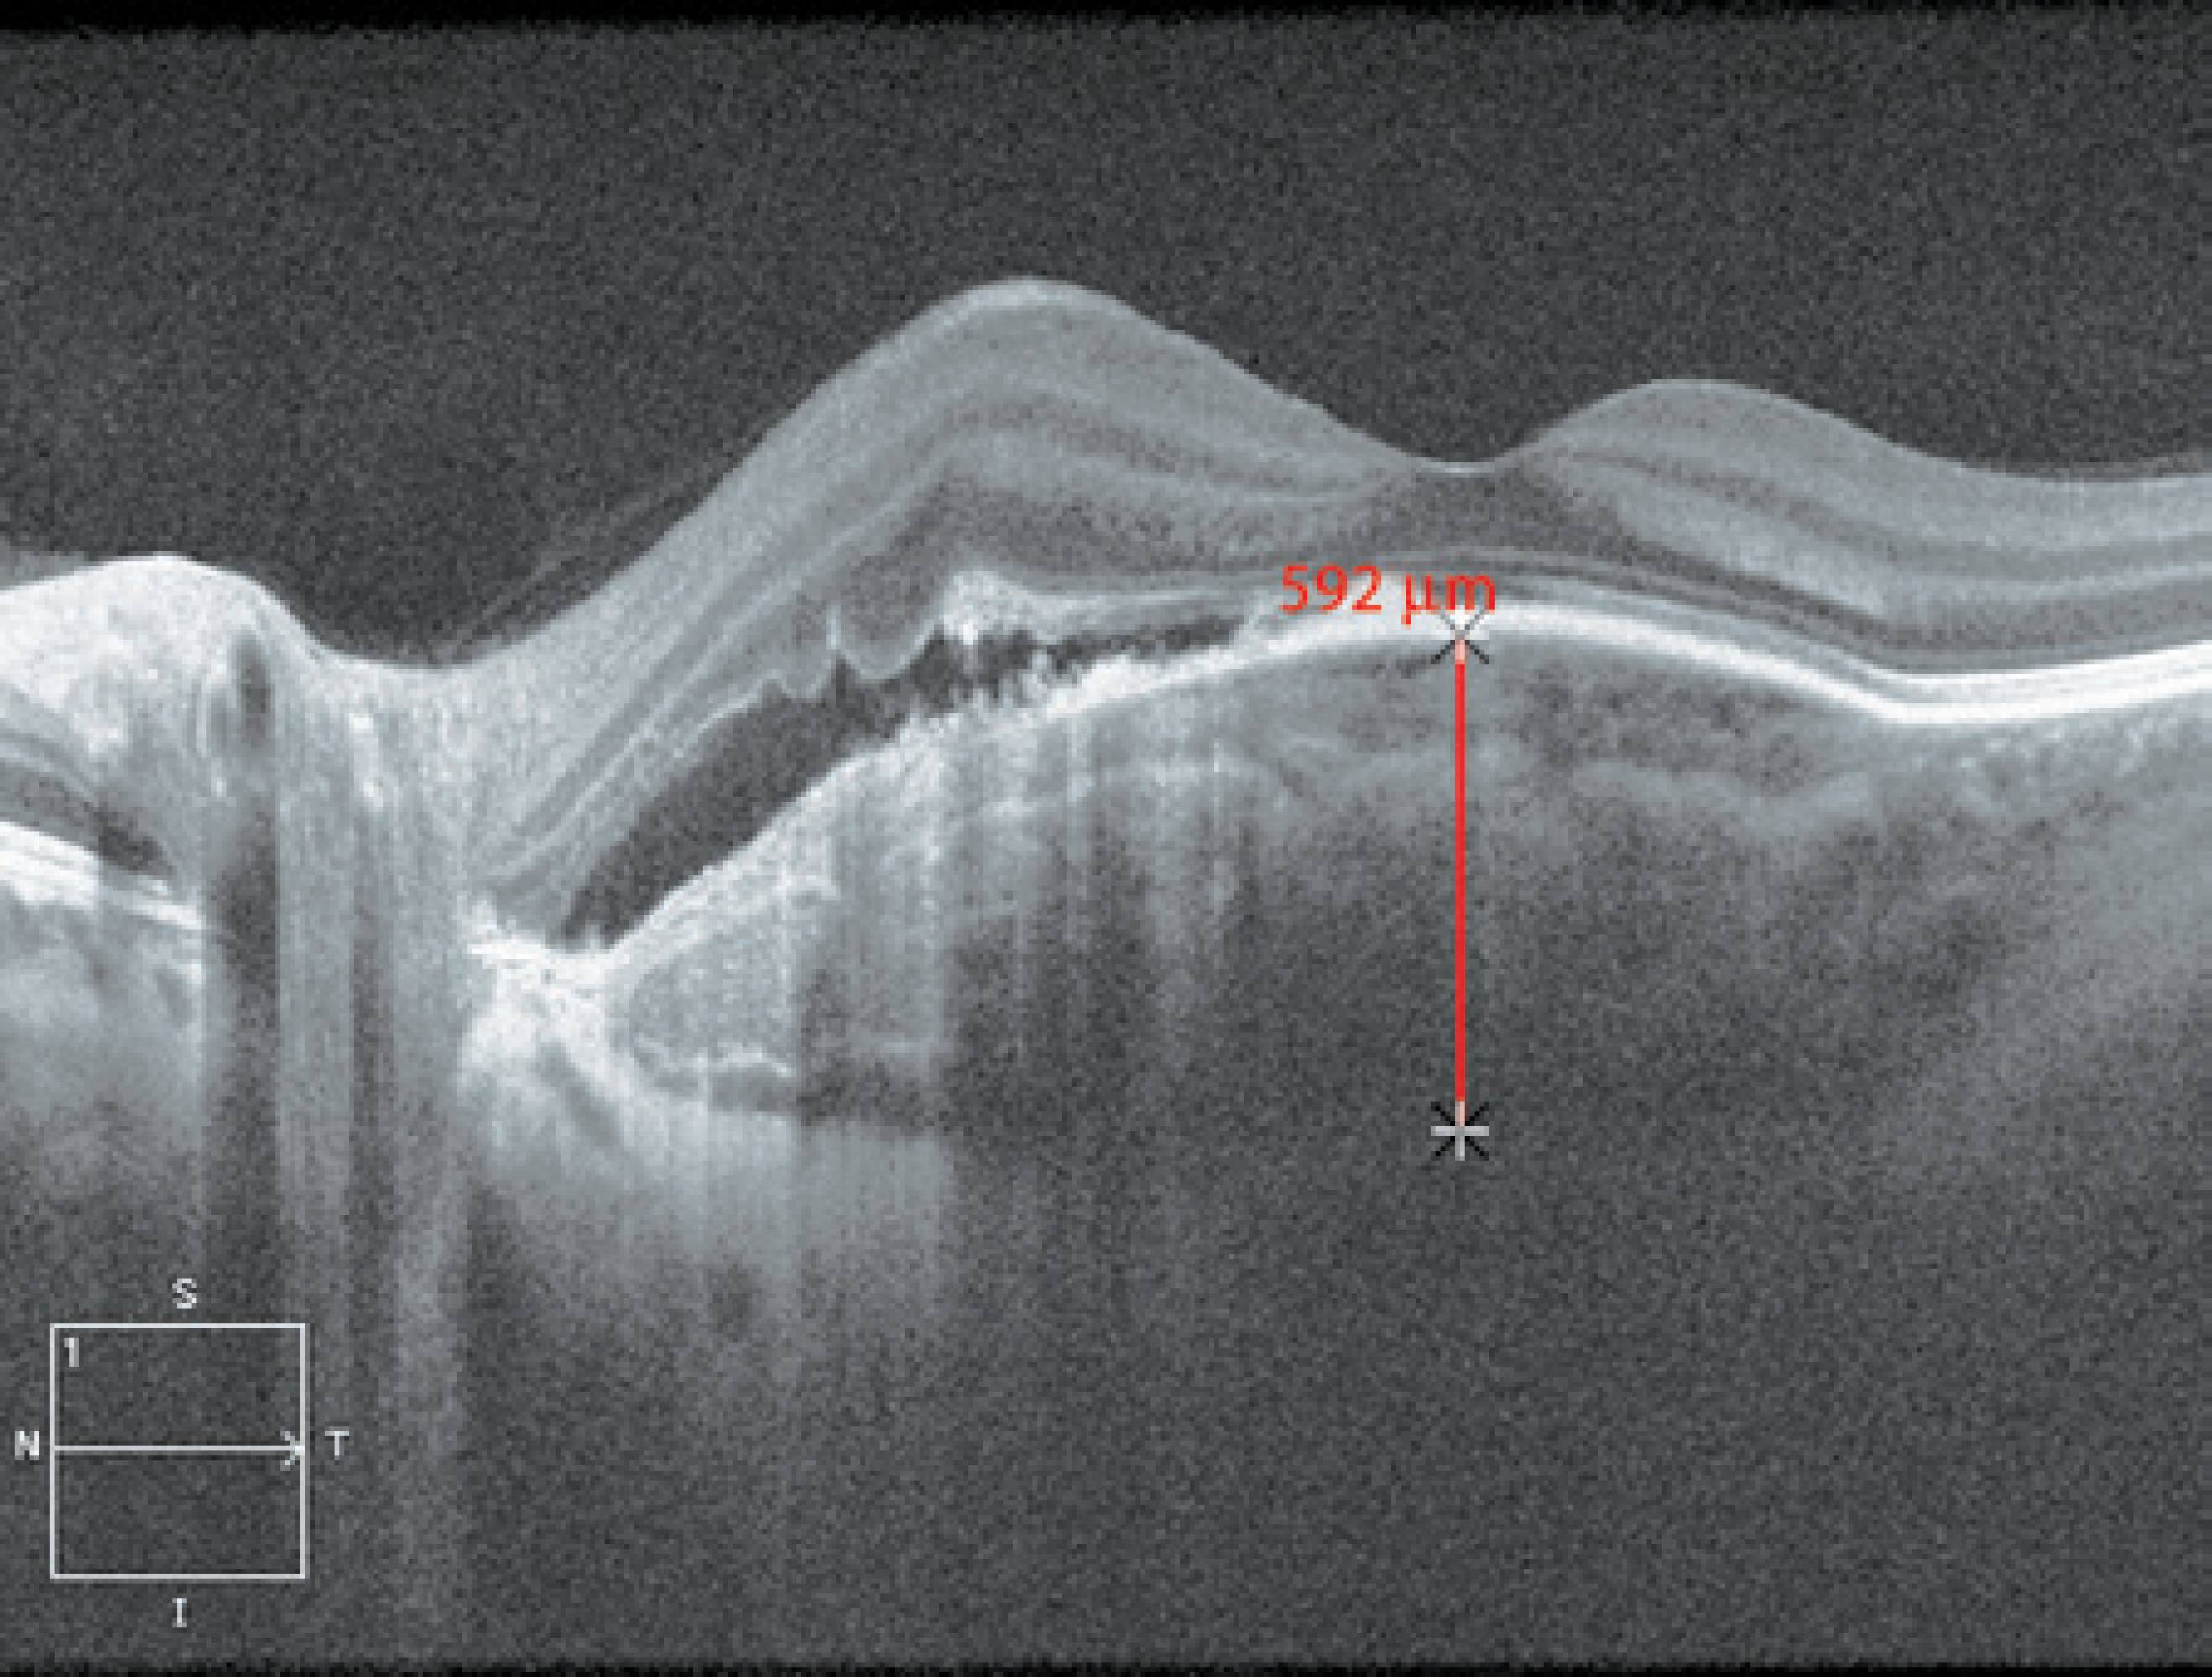

Figure 3 Enhanced depth imaging optical coherence tomography (EDI-OCT) images from case 1 affected by a choroidal osteoma with neovascular membrane. A multilayer configuration with a discrete sponge-like pattern was observed. The sclerochoroidal junction was detected, but we could not see it in all parts under the tumor because CNV had a fibrotic component that obscured the posterior part of the membrane. The choroidal thickness was 976 micra at the parafoveal area.

Figure 4 EDI-OCT images from case 2 affected by a choroidal osteoma with neovascular membrane. A multilayer configuration with a discrete sponge-like pattern was observed. The sclerochoroidal junction was detected in all parts of the tumor revealing a typical intrinsic transparency. The choroidal thickness was 592 micra at the foveal area.

EDI-OCT of the osteoma revealed a typical reflectivity pattern in both cases with the presence of hyperreflective horizontal lamellar lines, which were described in other reports(5,6). These characteristics could represent varying degrees of calcification within the tumor because of the different phases of bone tissue formation. We noticed multiple hyperreflective dots scattered in the hyporeflective matrix creating a sponge-like appearance as previously reported(6), but they were very subtle, especially under the CNV area. The sclerochoroidal junction was detected in both cases; however, in case 1, we were unable to detect it in all parts under the tumor because CNV had a fibrotic component that produced shadowing posterior to the membrane. The choroidal thickness was 976 micra in case 1 and 592 micra in case 2.